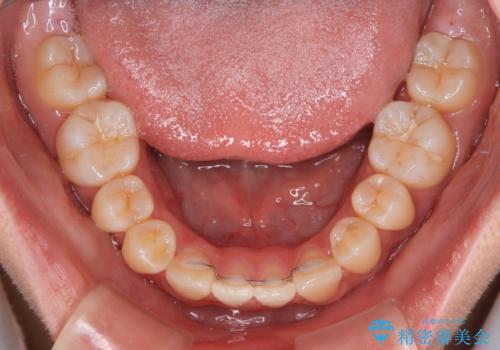

口元が引っ込みすぎることもなく、上下前歯がきれいに接触する位置に仕上げることができました。